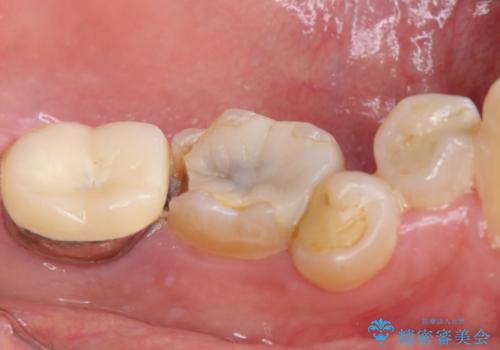

しっかりと咬むことができるようになり、喜んで頂けました。

他院ではお断りされたインプラント治療を行うことができ、ご満足頂けました。

インプラントの種類:ストローマン BLT

被せ物の種類:オールセラミッククラウン ベレッツァ